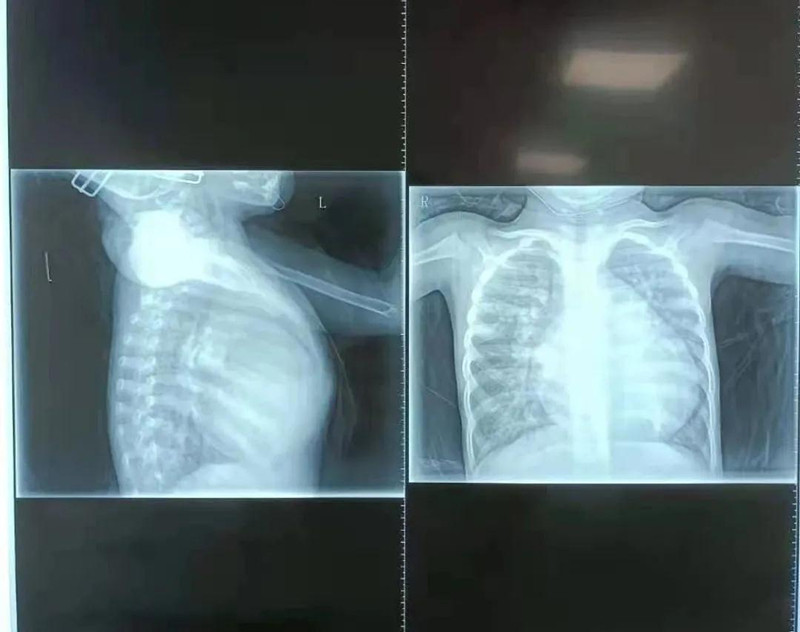

在蜜桃视频 小儿心脏病诊疗中心,杨明远医生初见馨馨印象极为深刻,4岁的孩子体重仅10.5公斤,由于心脏变大,她的胸骨被挤压得明显向前凸起。检查发现,馨馨心脏室间隔有直径17mm的缺损,导致左心室血液一部分流向右心室。同时,馨馨出生后动脉导管就未闭合,导致血液从主动脉分流到肺动脉。为了维持全身用血,左心室需要不断增加“劳动量”,而全身血液加上分流到右心室的血液最终都回到左心室,造成左心室严重增大,左室疏末径达到50.1mm,比正常成年人(正常成人左室疏末径为35-50mm)还要大。杨明远医生说,在先天性心脏病中,室间隔缺损比较常见,但像馨馨的心脏畸形严重到如此程度、对身体影响如此大的实属少见。